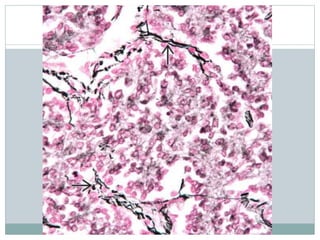

Architecture  Sheets (denselypacked)  Homer-Wright rosettes in PNET  Minimal intercellular collagen or reticulin  Rare myxoid change with microcyst formation  Necrosis with perivascular preservation of cells

• 16.

Histochemistry  PAS +ve intracytoplasmic glycogen in up to 75% of tumors  Reticulin -ve  Minimal or intercellular reticulin  vs lymphoma (cells), synovial sarcoma (small cell groups)

• #29 Intracytoplasmic glycogen in ES can be demonstrated by a periodic acid-Schiff (PAS) stain and is removed by pretreatment with diastase. Glycogen appears granular and brightly pink or magenta. Ewing sarcoma stained with PAS demonstrates red intracytoplasmic granules that represent glycogen. Note that not all cells are positive. Rhabdomyosarcoma contains glycogen, whereas lymphoma and neuroblastoma do not. EWS stained with PAS-D is shown. The diastase digests the glycogen, confirming that intracytoplasmic material is not some other type of complex carbohydrate.

• #30 A reticulin stain of Ewing sarcoma shows that groups of cells, and not individual cells, are surrounded by reticulin fibers . Reticulin fibers surround individual cells in lymphoma (previously known as "reticulum cell sarcoma").

• #31 Reticulin fibers are seen around blood vessels and between tumor lobules in ES; however, these fibers are absent between neoplastic cells. By contrast, reticulin often surrounds small groups of cells in the morphologically similar, poorly differentiated synovial sarcoma.